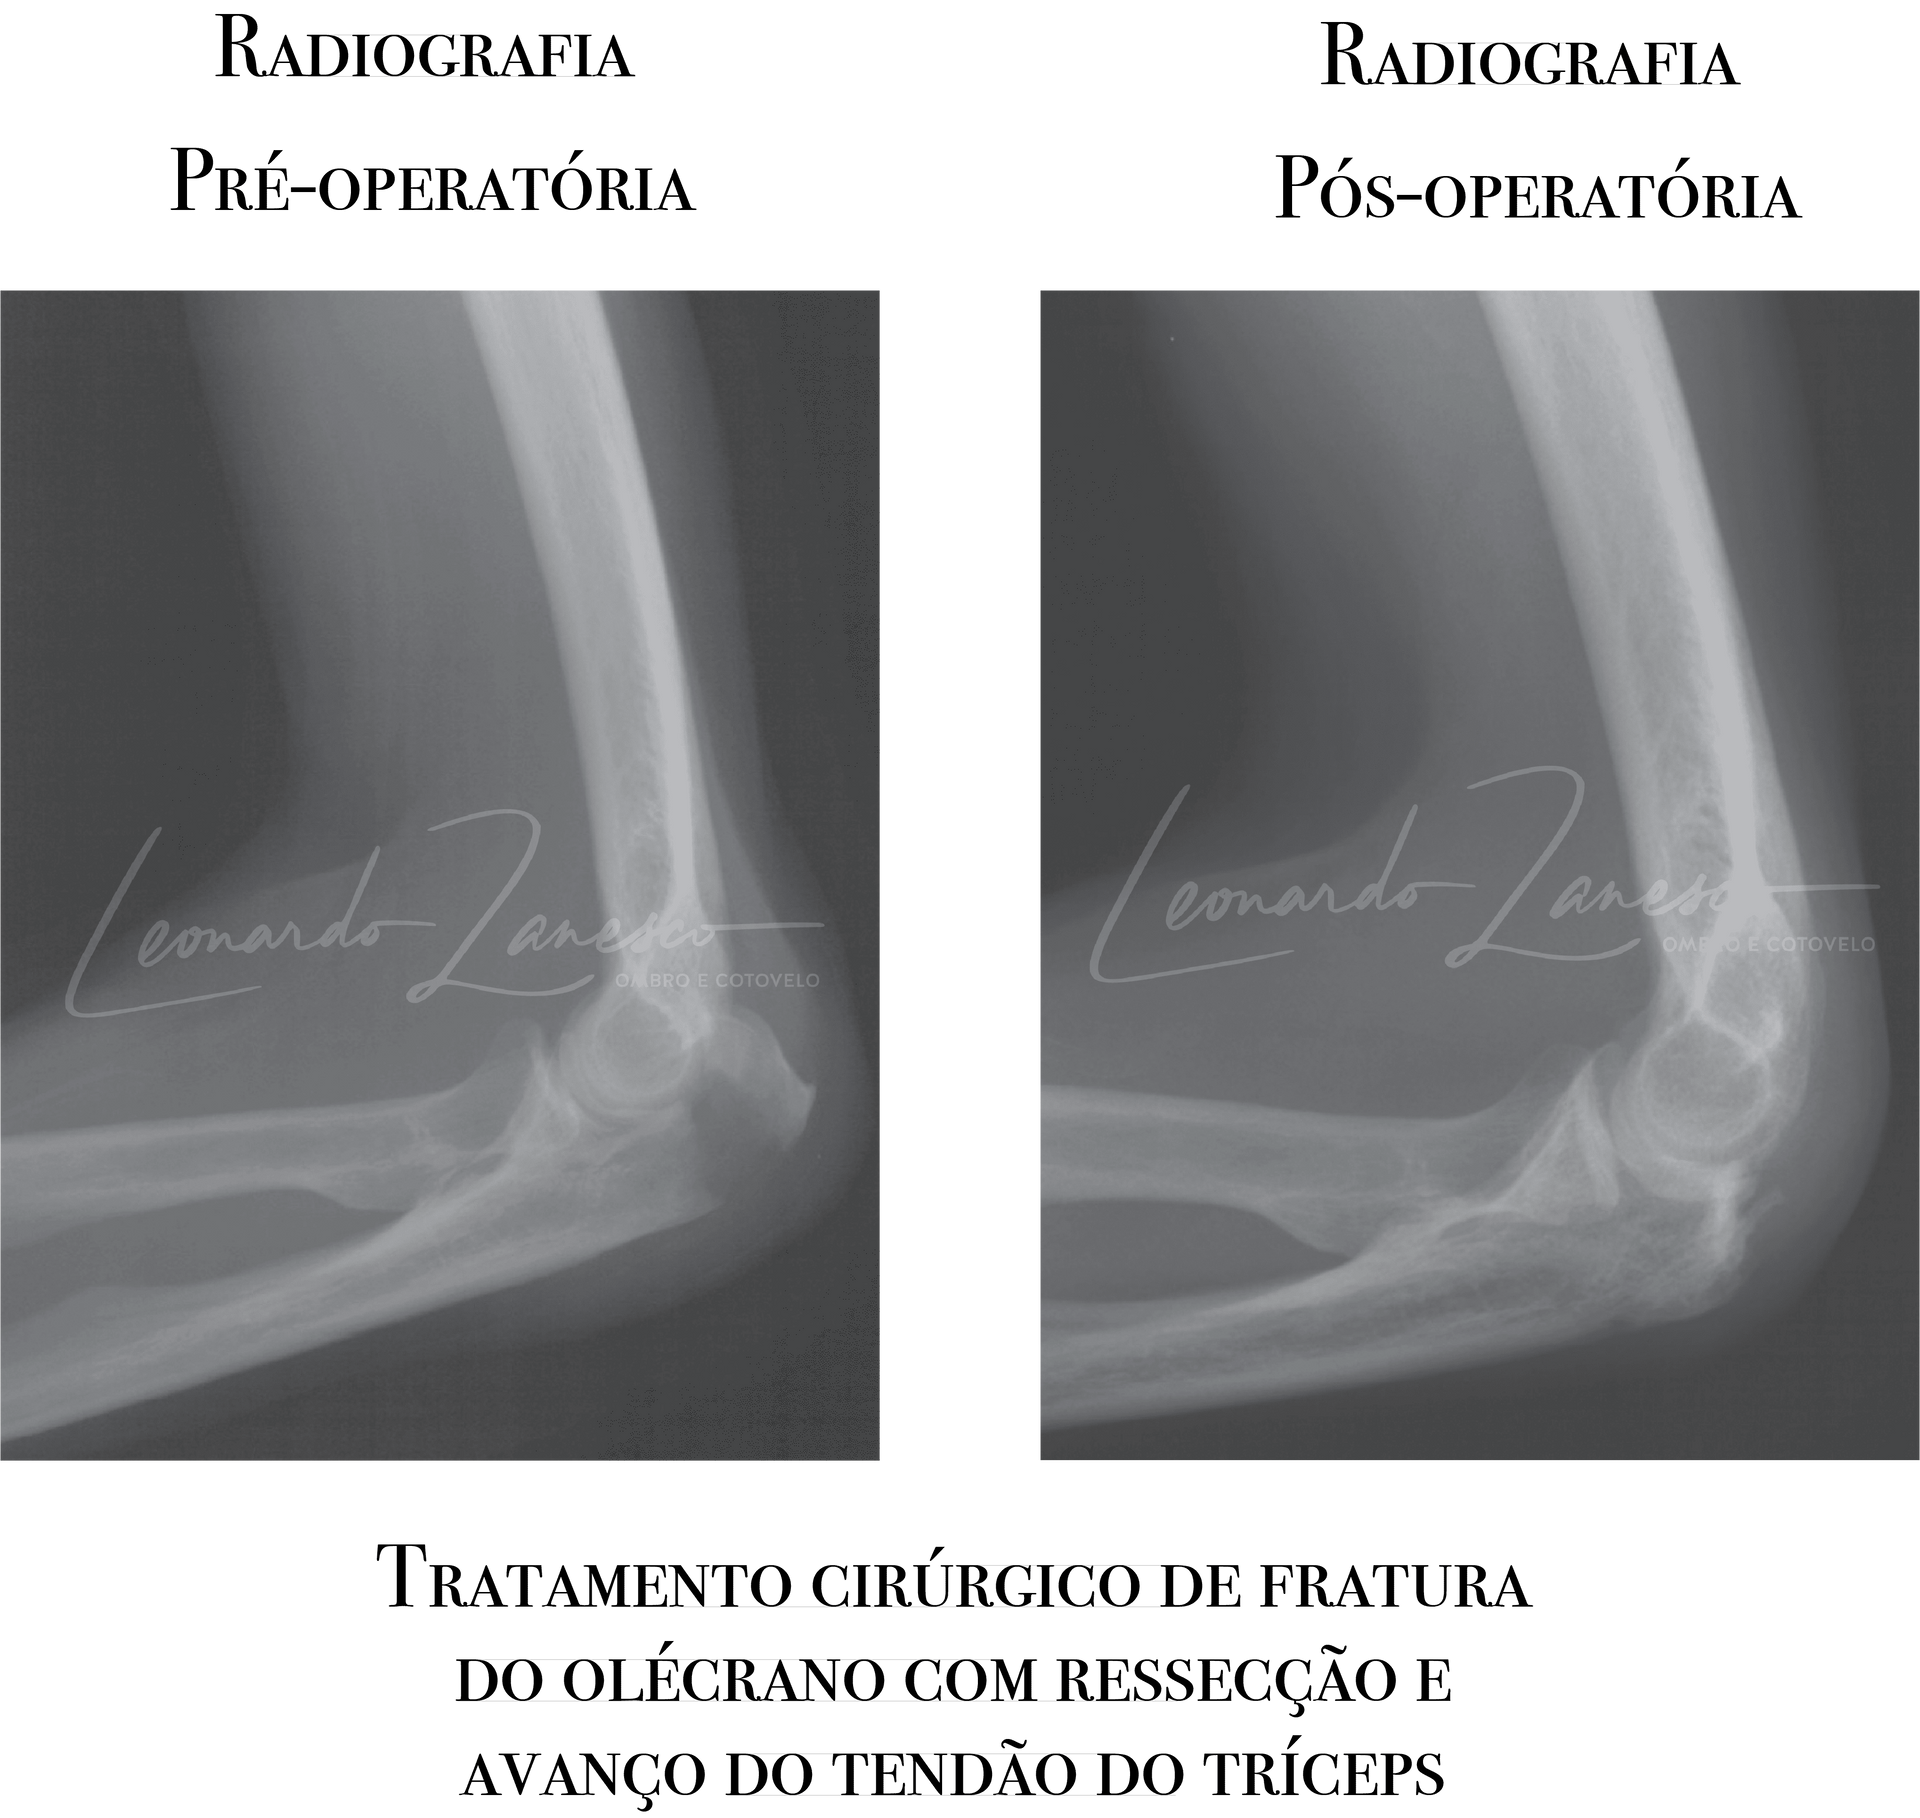

Ressecção do fragmento fraturário e avanço do tendão do tríceps:

Opção para pacientes de idade avançada e baixa demanda, quando a fratura é muito fragmentada e

não viável à reconstrução. A literatura alerta que

ressecções muito extensas podem desestabilizar o cotovelo; por isso, esse procedimento é reservado a

fragmentos menores e casos selecionados. Em geral ressecções de fragmentos menores que 25% são seguras e podem ser consideradas em casos selecionados com tamanho até 50%